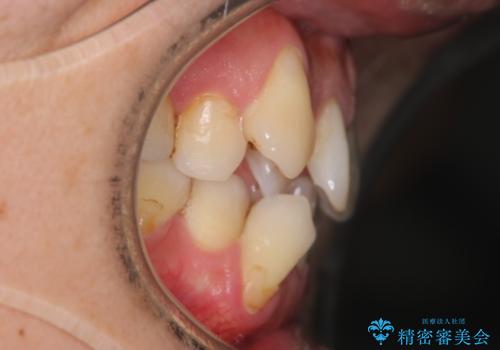

- 治療計画

叢生量が大きいため、上下顎両側4番を抜歯しました。矯正治療による歯肉退縮の著しい悪化もなく、主訴であるガタつきも改善できました。